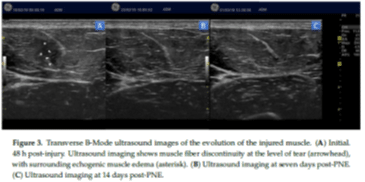

Diagnostic Musculoskeletal Ultrasound (MSKUS) is a safe and painless imaging technique that utilizes sound waves to produce high-resolution images of the musculoskeletal system. Unlike traditional imaging methods like X-rays or MRI, MSK US provides dynamic, real-time visualization of structures in motion, allowing for a comprehensive assessment of function and pathology. Furthermore, there is no radiation with MSK US as opposed to MRI or X-rays.

1. Precision Diagnosis: MSK US offers unparalleled detail, allowing for precise localization and characterization of musculoskeletal abnormalities such as tears, inflammation, cysts, and fluid collections.

2. Dynamic Assessment: Unlike static imaging techniques, MSKUS captures real-time movement, enabling dynamic evaluation of joint mechanics, muscle function, and tendon gliding.

• Muscle Injuries: Sprains, tears, contusions, and muscle atrophy.